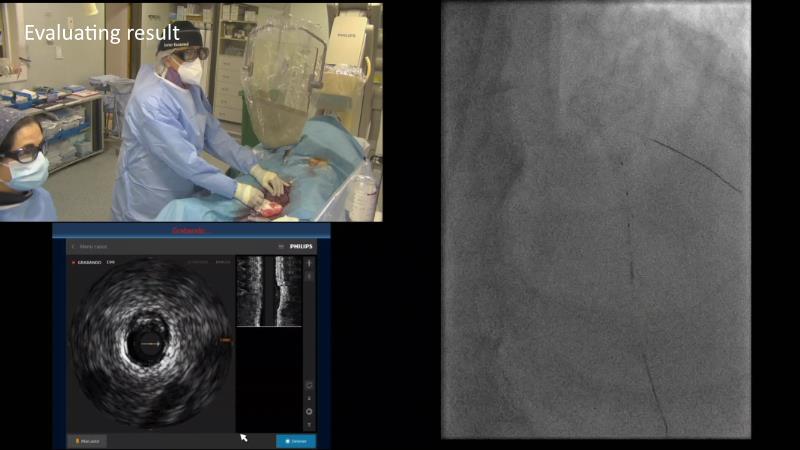

Discover the indispensable toolset of ultra-low contrast (ULC) percutaneous coronary intervention (PCI) in complex coronary interventions and higher-risk patients in this session. Gain a comprehensive understanding of how ULC PCI can enhance the safety and quality of revascularization in complex procedures and learn practical aspects from recorded cases, including specific approaches utilizing intracoronary imaging, physiology, and dedicated tools and techniques.

- To learn practical aspects from recorded ULC PCI cases, including specific approaches using intracoronary imaging, physiology and dedicated tools and techniques